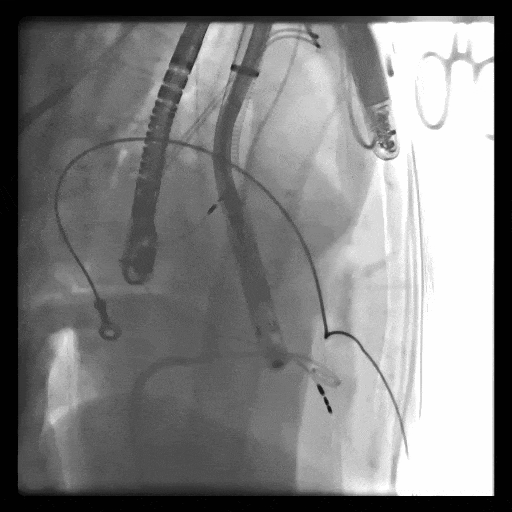

術(shù)中DSA顯示起搏器導(dǎo)線的干擾,右心室造影確定瓣環(huán)位置,操作空間小